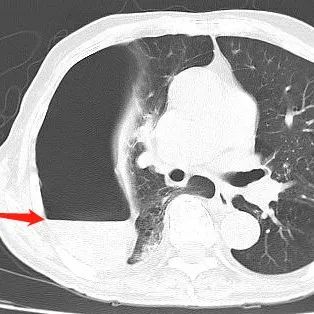

学会鉴别肺大疱和气胸以及气胸和肺大疱合并感染非常重要有位来自江苏的同仁在微信群里发了一个很有意思的病例咨询:患者男,85岁,有慢阻肺、双肺肺大疱多年,平日休息状态下呼吸困难不明显,但活动易出现气促,本次主因咯血入院,查胸部CT出现新的变化:(肺窗视频)(纵膈窗视频)这里给大家留一个思考题:根据目前仅提供的病历资料,你认为这是液气胸还是肺大疱合并感染?大家思考选择后在往下看哦!这个病例很具有代表性,在临床上掌握鉴别肺大疱和气胸,以及鉴别肺大疱合并感染和液气胸非常重要,因为如果是液气胸,不赶紧做胸穿,患者可能会很危险,但如果是肺大疱合并感染误当做液气胸来穿刺,后果会非常严重,不堪设想。...